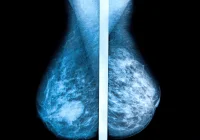

The study was structured as a retrospective cohort analysis involving 116,495 women aged 50 to 69. These participants had no previous history of breast cancer and had undergone at least three consecutive biennial screening rounds within BreastScreen Norway from 2004 to 2018. The screenings were conducted across nine breast centres using standard mammography procedures. The AI tool applied in this investigation was Lunit INSIGHT MMG, a commercially available algorithm that provides a continuous score indicating the likelihood of cancer presence. The scores range from 0 to 100, with higher numbers representing a greater probability of cancer. The study sought to evaluate whether the algorithm’s scores could effectively identify imaging features that indicate cancer development years in advance.

The study found distinct differences in AI scores between women who later developed cancer and those who did not. Notably, the mean AI score for breasts that eventually developed screening-detected cancer rose significantly across the three study rounds, from 19.2 in the first round to 82.7 in the third. For interval cancers, the scores were comparatively lower but still notable, indicating that the algorithm could recognise subtle pre-cancerous signs even when radiologists could not.

One of the most compelling findings was the rapid increase in the AI scores leading up to the third screening round for women who developed screening-detected cancer. This pattern suggests that AI can identify progressive changes in mammograms that precede clinical diagnosis. The AUC values, used to assess the discriminatory power of the AI tool, improved significantly by the third round, reaching 0.97 for screening-detected cancer and 0.78 for interval cancers. This demonstrates that the AI algorithm had high accuracy in distinguishing between breasts that would and would not develop cancer, especially close to the time of detection.